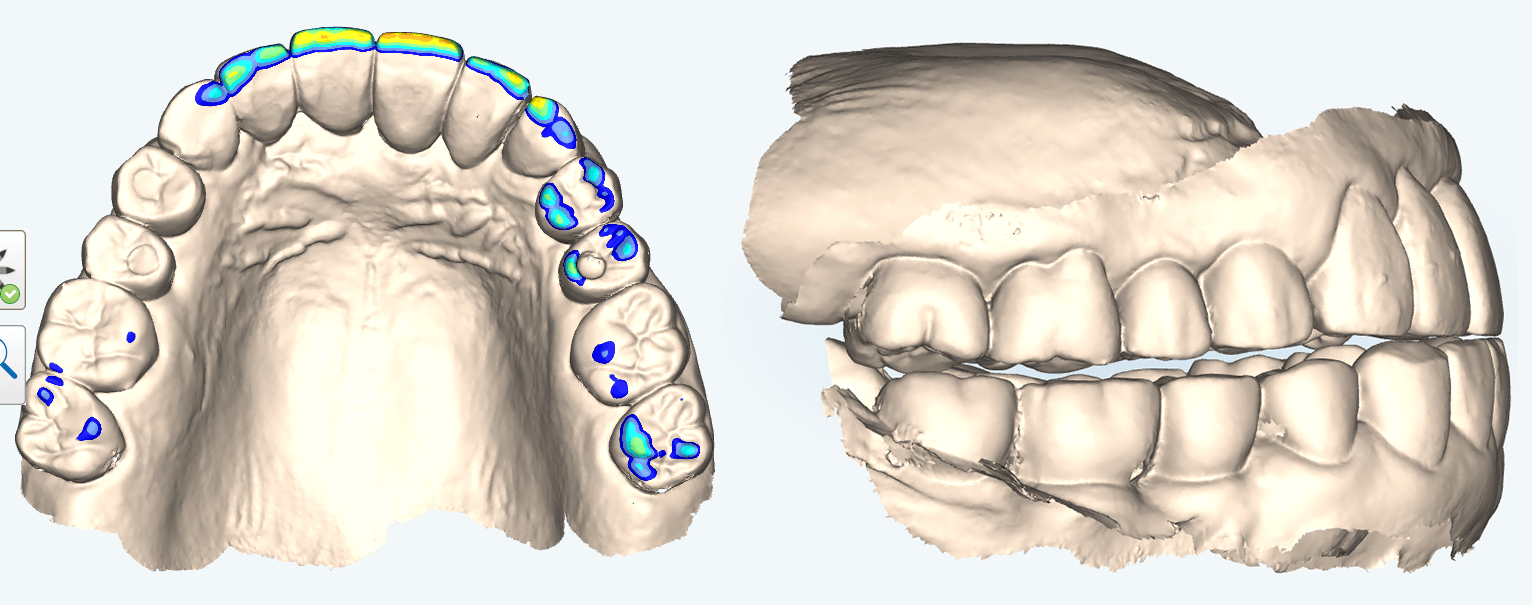

当院では、体の歪みを調べ、その方にとって無理のない安定した顎位を見つけ出し、その位置で噛み合わせを構築することを重要視した矯正治療を行っています。

足の長さのずれは整体で治りますが、次の日にはまた戻ってしまいます。

しかし、整体された状況下で顎の位置の記録をとることで、姿勢は崩れにくくなります。